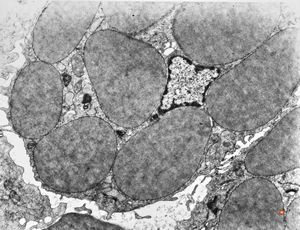

M,44y. | spleen - Gaucher disease